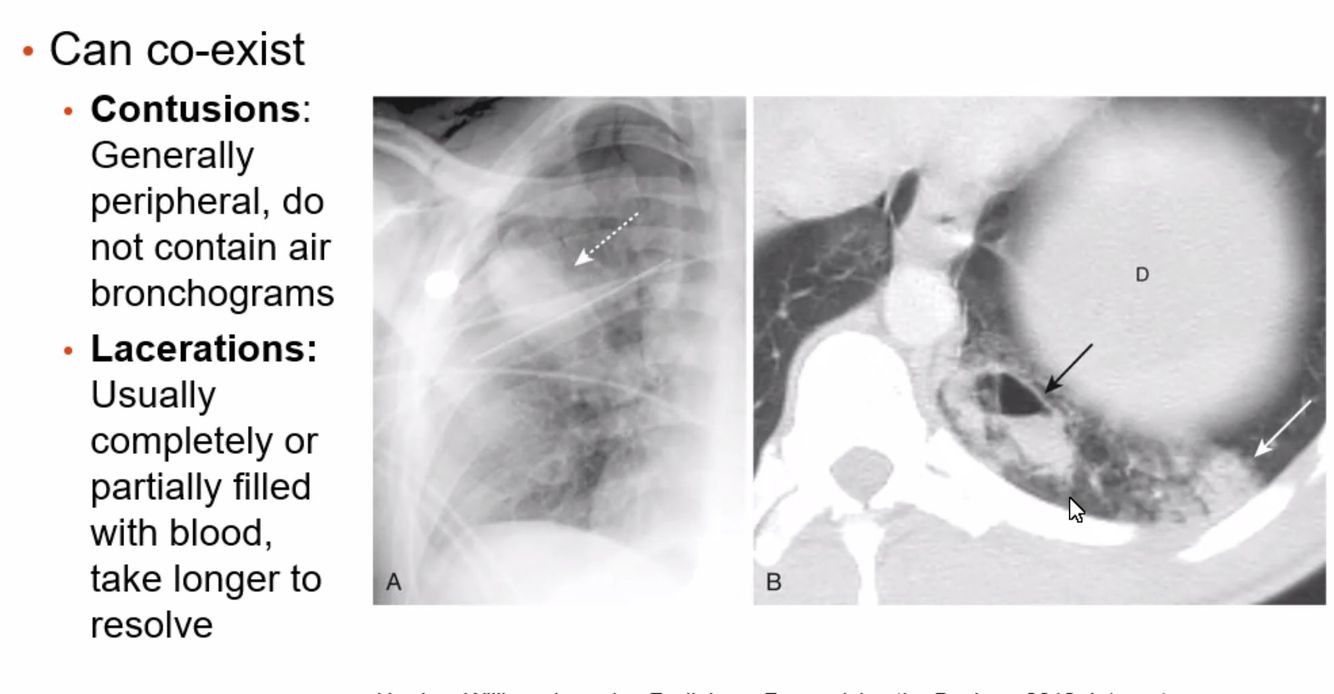

Lung laceration